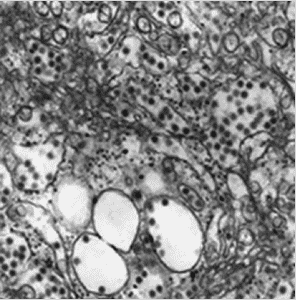

The virus itself is part of the Flaviviridae family of viruses of which several are harmful to the human body like Omsk Haemorrhagic Fever, Eastern Equine Encephalitis and Japanese Bourne Encephalitis for example.